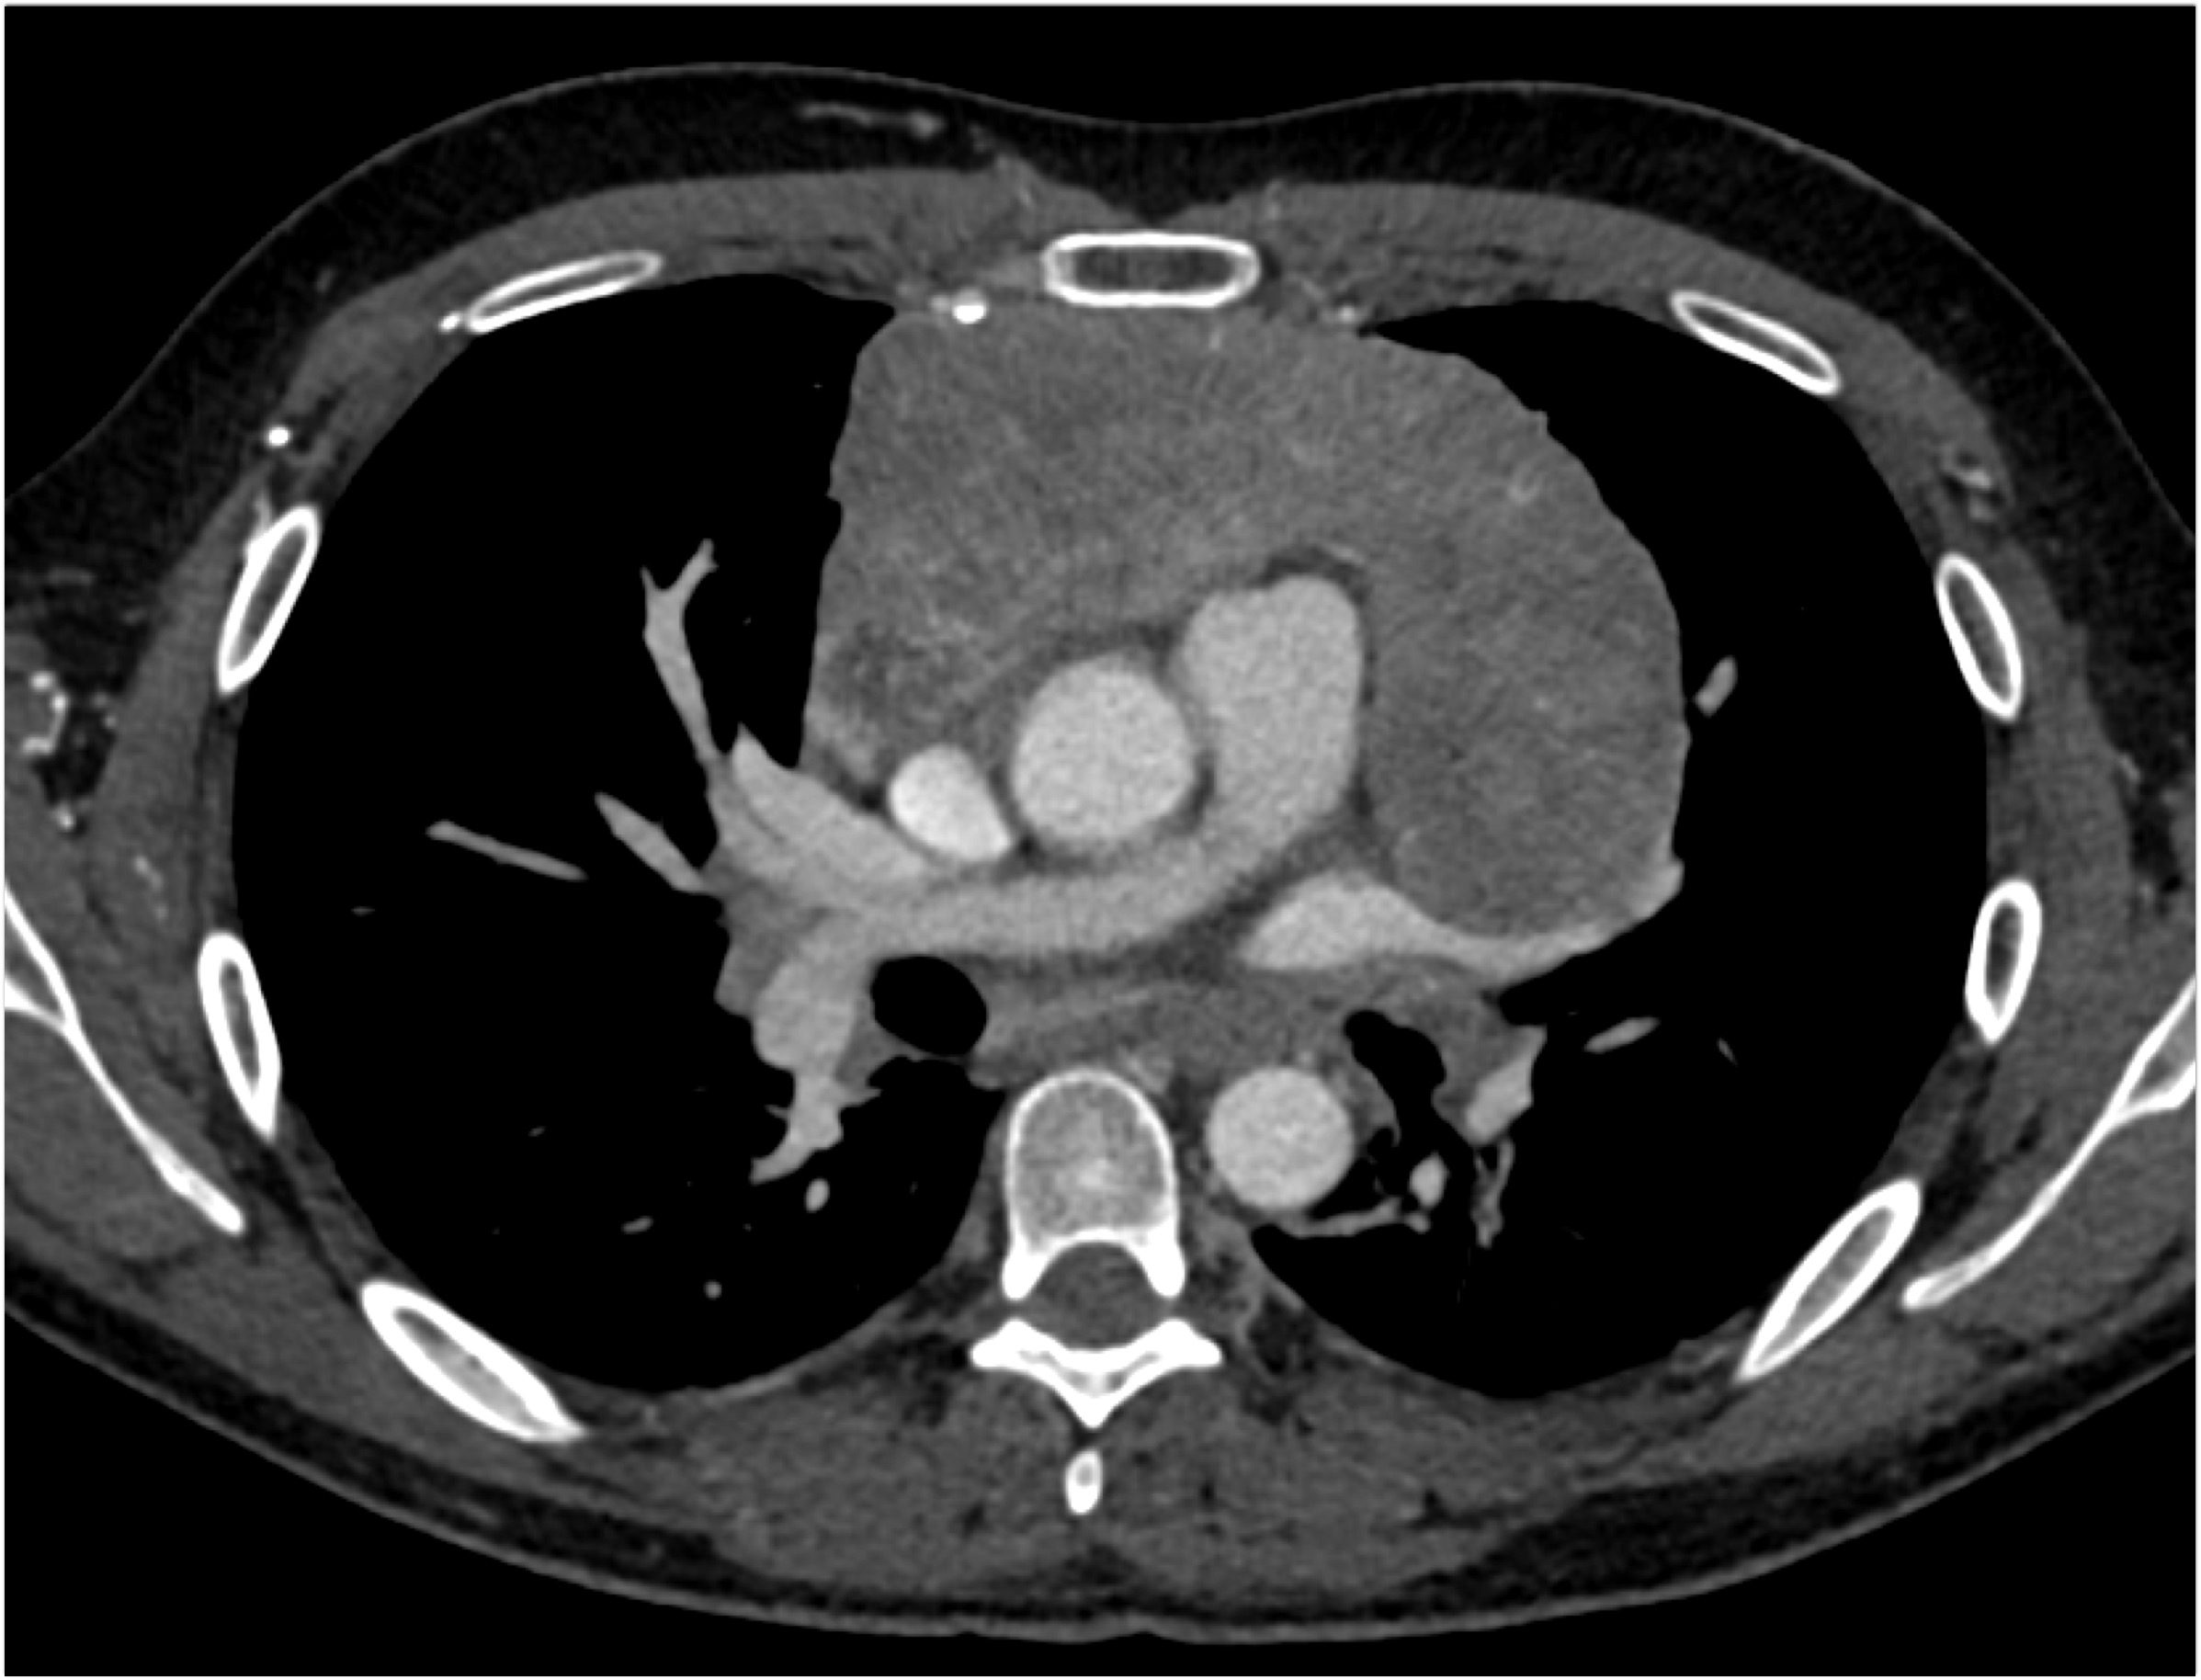

- Evaluate the CT images of each question carefully.

- Click on thumbnail images to view a larger version of the images.

- Take time to make the call on the diagnosis for each individual question.